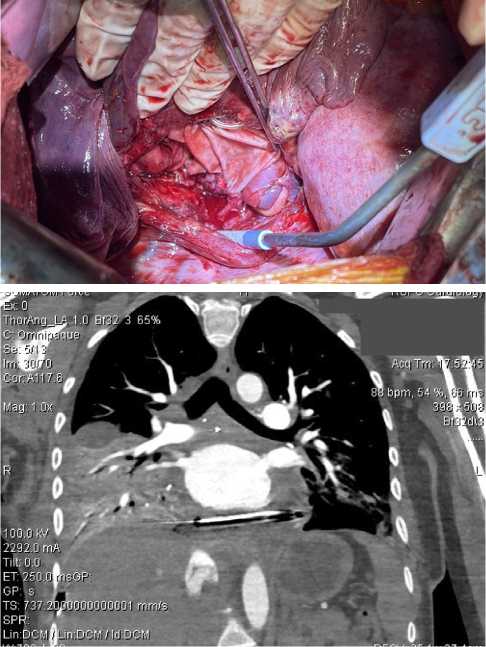

На втором этапе операции выполнен мультипортальный доступ справа. Начата мобилизация опухоли. Однако развилась десатурация до 75 %, которая потребовала перехода на двухлегочную вентиляцию и увеличения фракции кислорода во вдыхаемой смеси до 80 %. Заподозрена травма мембранозной части трахеи. Интраоперационно выполнена диагностическая фибробронхоскопия, травма исключена. Ввиду непереносимости однолегочной вентиляции продолжена двухлегочная ИВЛ, выполнена торакотомия справа. Произведено клипирование дренирующих опухоль вен в паратрахеальной области. При дальнейшей ревизии выявлена связь опухоли с задней стенкой левого предсердия (рис. 3). Для выполнения радикальной операции требовалась резекция левого предсердия в условиях искусственного кровообращения (ИК), что невозможно в условиях РНПЦ ОМР, в связи с чем операция была завершена. При манипуляциях с опухолью отмечались неоднократные подъемы артериального давления до 180/110 мм рт. ст и ЧСС до 120/мин, которые купировались в течение 5–10 мин. после прекращения манипуляций с опухолью.

Рис. 3. Инвазия опухоли в левое предсердие (интраоперационное фото)

Fig. 3. Tumor invasion into the left atrium (intraoperative photo)

Рис. 4. Вид после завершения реконструкции предсердия бычьим перикардом: А — интраоперационное фото; Б — КТА-ОГК после операции

Fig. 4. View after completion of atrial reconstruction with bovine pericardium: A — intraoperative photo; Б — postoperative thoracic CTA

На 2 послеоперационные сутки диагностирована полисегментарная пневмония, которая разрешилась на 9 сут. Пациентка выписана на 10 сут. после операции. Объем левого предсердия и его функция адекватные, по результатам ЭХО-КГ и КТ-ангиографии (рис. 4).